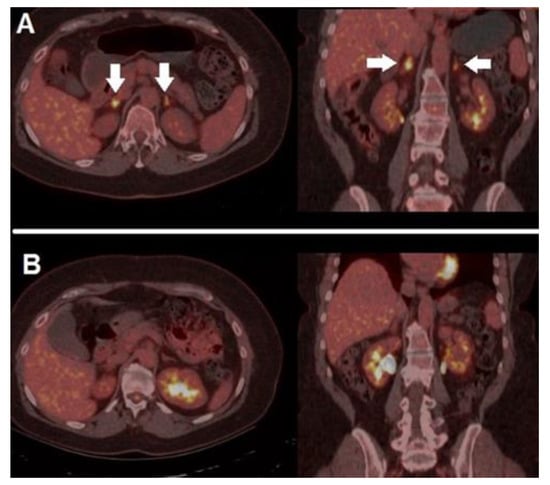

- Sachpekidis, C.; Anwar, H.; Winkler, J.K.; Kopp-Schneider, A.; Larribere, L.; Haberkorn, U.; Hassel, J.C.; Dimitrakopoulou-Strauss, A. Longitudinal Studies of the 18F-FDG Kinetics after Ipilimumab Treatment in Metastatic Melanoma Patients Based on Dynamic FDG PET/CT. Cancer Immunol. Immunother. 2018, 67, 1261–1270. [Google Scholar] [CrossRef] [PubMed]

- Sachpekidis, C.; Kopp-Schneider, A.; Hakim-Meibodi, L.; Dimitrakopoulou-Strauss, A.; Hassel, J.C. 18F-FDG PET/CT Longitudinal Studies in Patients with Advanced Metastatic Melanoma for Response Evaluation of Combination Treatment with Vemurafenib and Ipilimumab. Melanoma Res. 2019, 29, 178–186. [Google Scholar] [CrossRef]